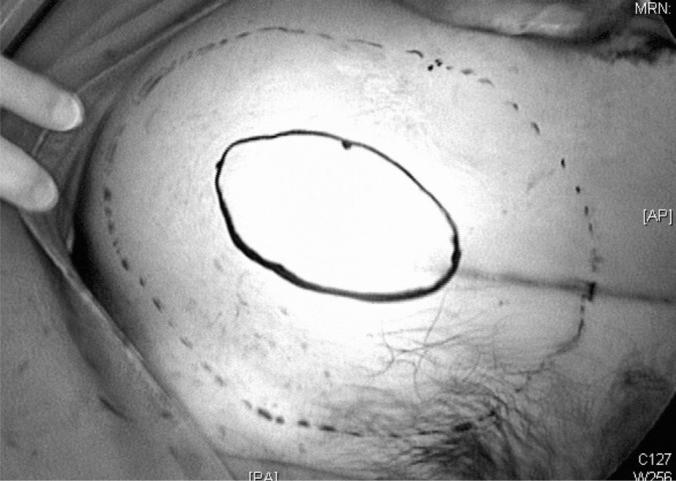

Three patients with incisional hernias after gynecologic surgery underwent laparoendoscopic single-site totally extraperitoneal procedures. We evaluated the patients' preoperative and postoperative condition, as well as the details of their original surgery. We performed the procedure through a 2-cm umbilical incision followed by mesh insertion and transabdominal suture placement in all patients.